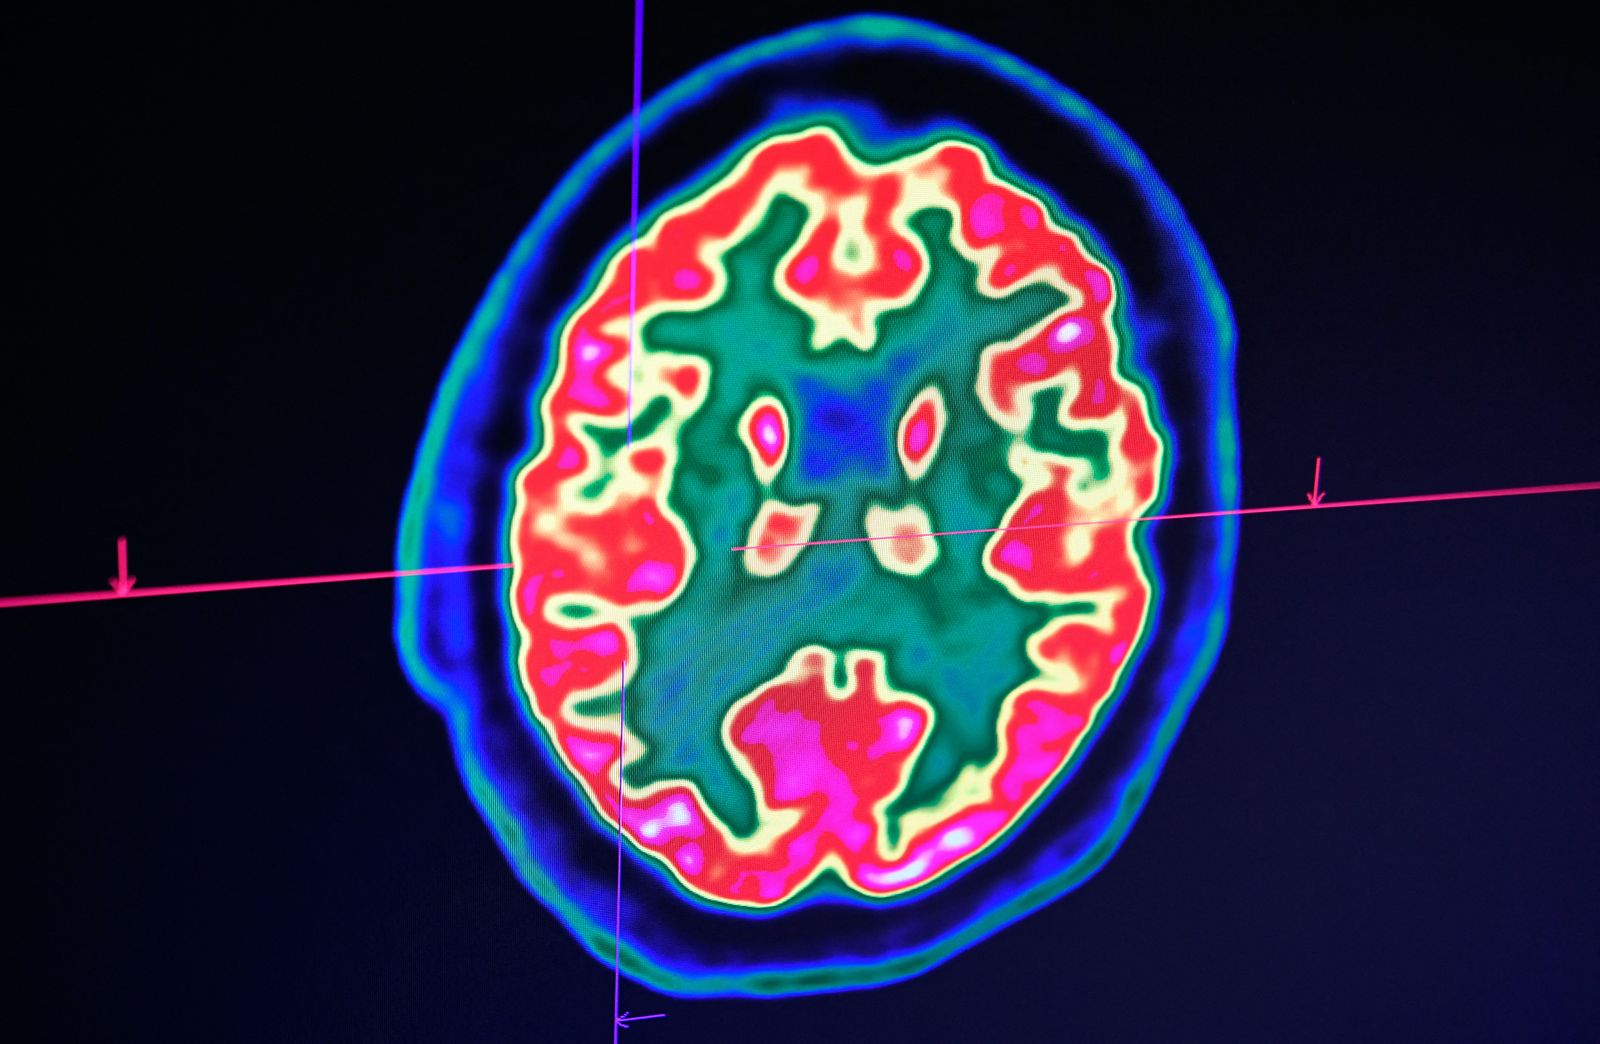

تشمل السكتات الدماغية نوعين رئيسيين، إذ تعد السكتات الإقفارية الأكثر شيوعاً، بينما تعتبر السكتات النزفية أكثر خطورة وغالباً ما تكون أكثر فتكاً.